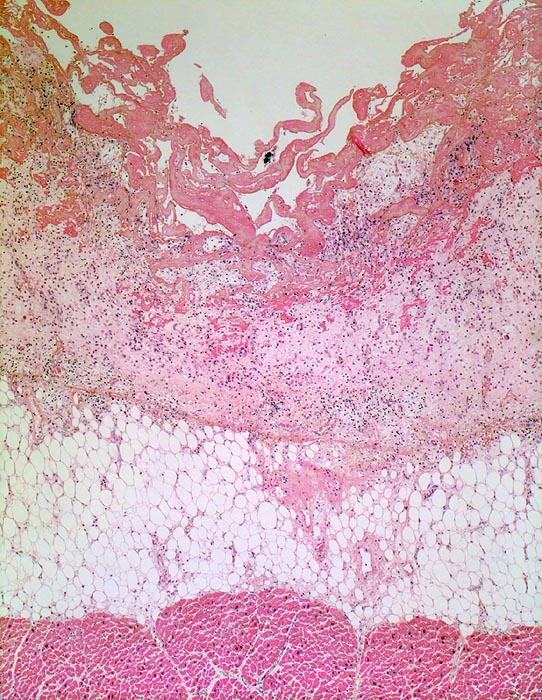

PathoPic ID 4532 - fibrinöse Perikarditis

fibrinöse Perikarditis

Entzündung / Reparatur

Perikard

Körperhöhlen, Serosa

Das Epikard bedeckt von

Fibrin. Das Fibrin wird von

Granulationsgewebe organisiert.

Epikardiales Fettgewebe und

Myokard.

Patientin verstorben in Urämie.

Nach Abschluss der Organisation bleiben fibröse Perikardverwachsungen zurück (Narbe).

Vergrösserung

25